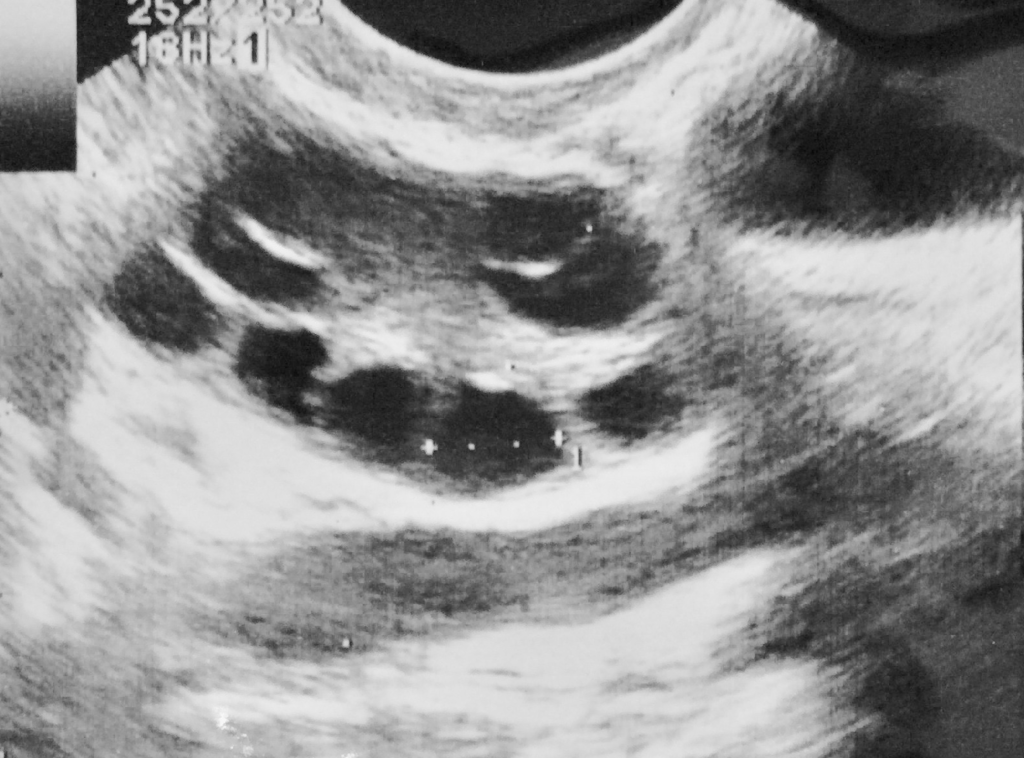

• 卵巣内に小さな、痛みのない、液体で満たされた嚢が形成されること

• 卵巣の外殻の肥厚